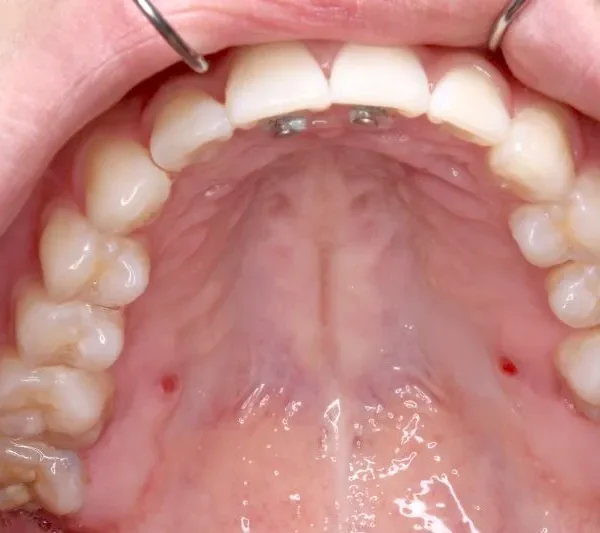

初診時年齢 小学校6年生 (女性) 主訴 犬歯がずれている・噛み合わない

診断名 叢生・交叉咬合 装置名

マルチブラケット装置

歯科矯正用アンカースクリュー

右下の犬歯がずれて生え噛み合わせの邪魔をしています。

歯は抜かず、上下マルチブラケット装置を使用し治療いたしました。

治療回数54回、9年3ヶ月の治療期間で矯正治療を終了しました。